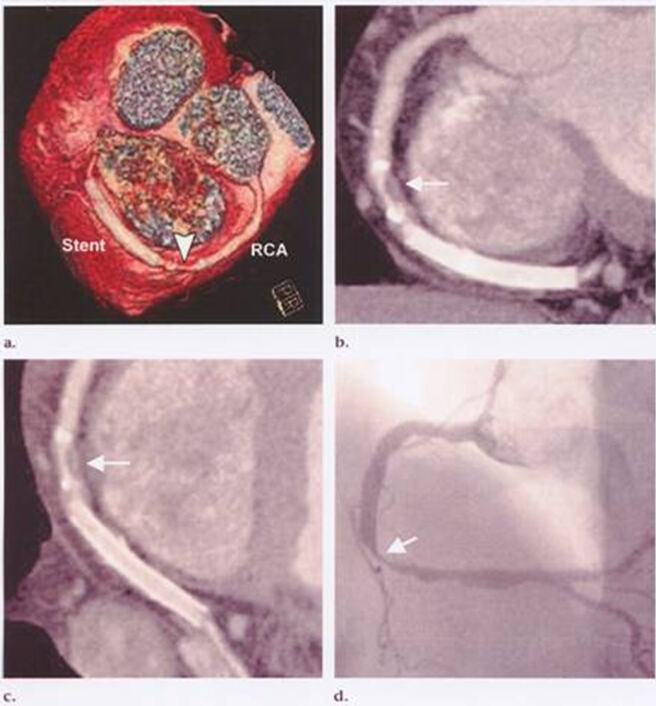

1.癥狀很典型或很不典型都不是CT的適應癥,如果病人癥狀很不典型,沒有支持冠心病的證據(jù),可以先做一些更簡單的檢查,如活動平板或24小時心電圖等檢查。相反,如果癥狀很典型則應該直接做造影,而造影檢查的同時可以進行球囊擴張或支架植入的手術。所以說,CT的價值主要在于鑒別那些懷疑有冠心病,但證據(jù)又不是很足的患者。如果是冠脈支架術后的復查或冠脈搭橋術后評估,就不用再去做造影了,直接冠脈CT就可解決問題了。

2. 有些病變CT檢查看不清楚:并非所有的病變CT都能看清,尤其是對于某些鈣化比較明顯或是植入過支架的患者,心率快慢也會明顯影響成像質量,心率越快成像質量越差,目前的冠脈CT檢查要求心率盡量控制在70次/分以下。對于某些患者冠脈CT還可能高估病變的狹窄程度。相信隨著技術的進步,冠脈CT的成像質量和適用范圍也必將大大提高。